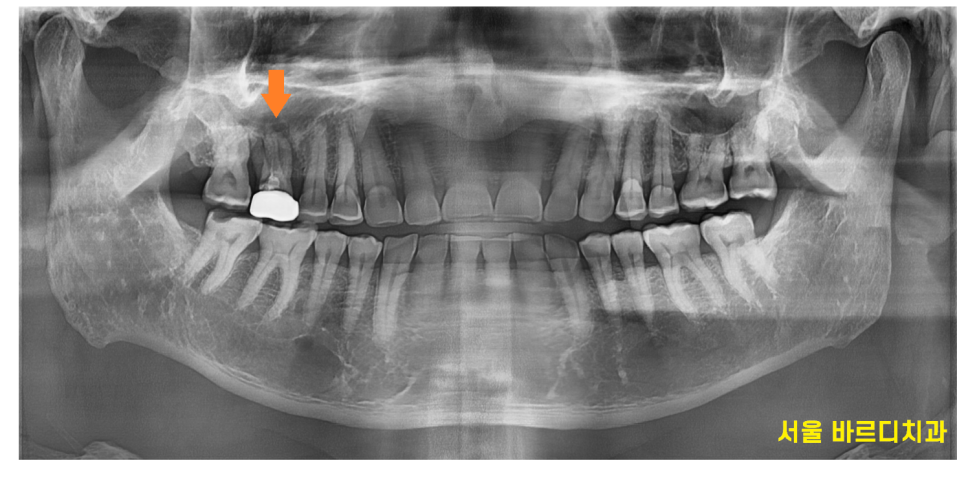

검사를 위해 촬영해본 x ray

오른쪽 위에 어금니 1개가 잇몸뼈가 심하게 녹아있습니다.

잇몸뼈가 남아있는 양 옆 치아와 비교해보아도

유독 문제 치아 주변으로만 까만 것이 보이실겁니다.

뼈가 다 녹아서 그렇습니다.

x-ray 상에서 뼈가 너무 많이 녹아있어

임플란트.. 바로는 어렵겠다... 감이 왔습니다.